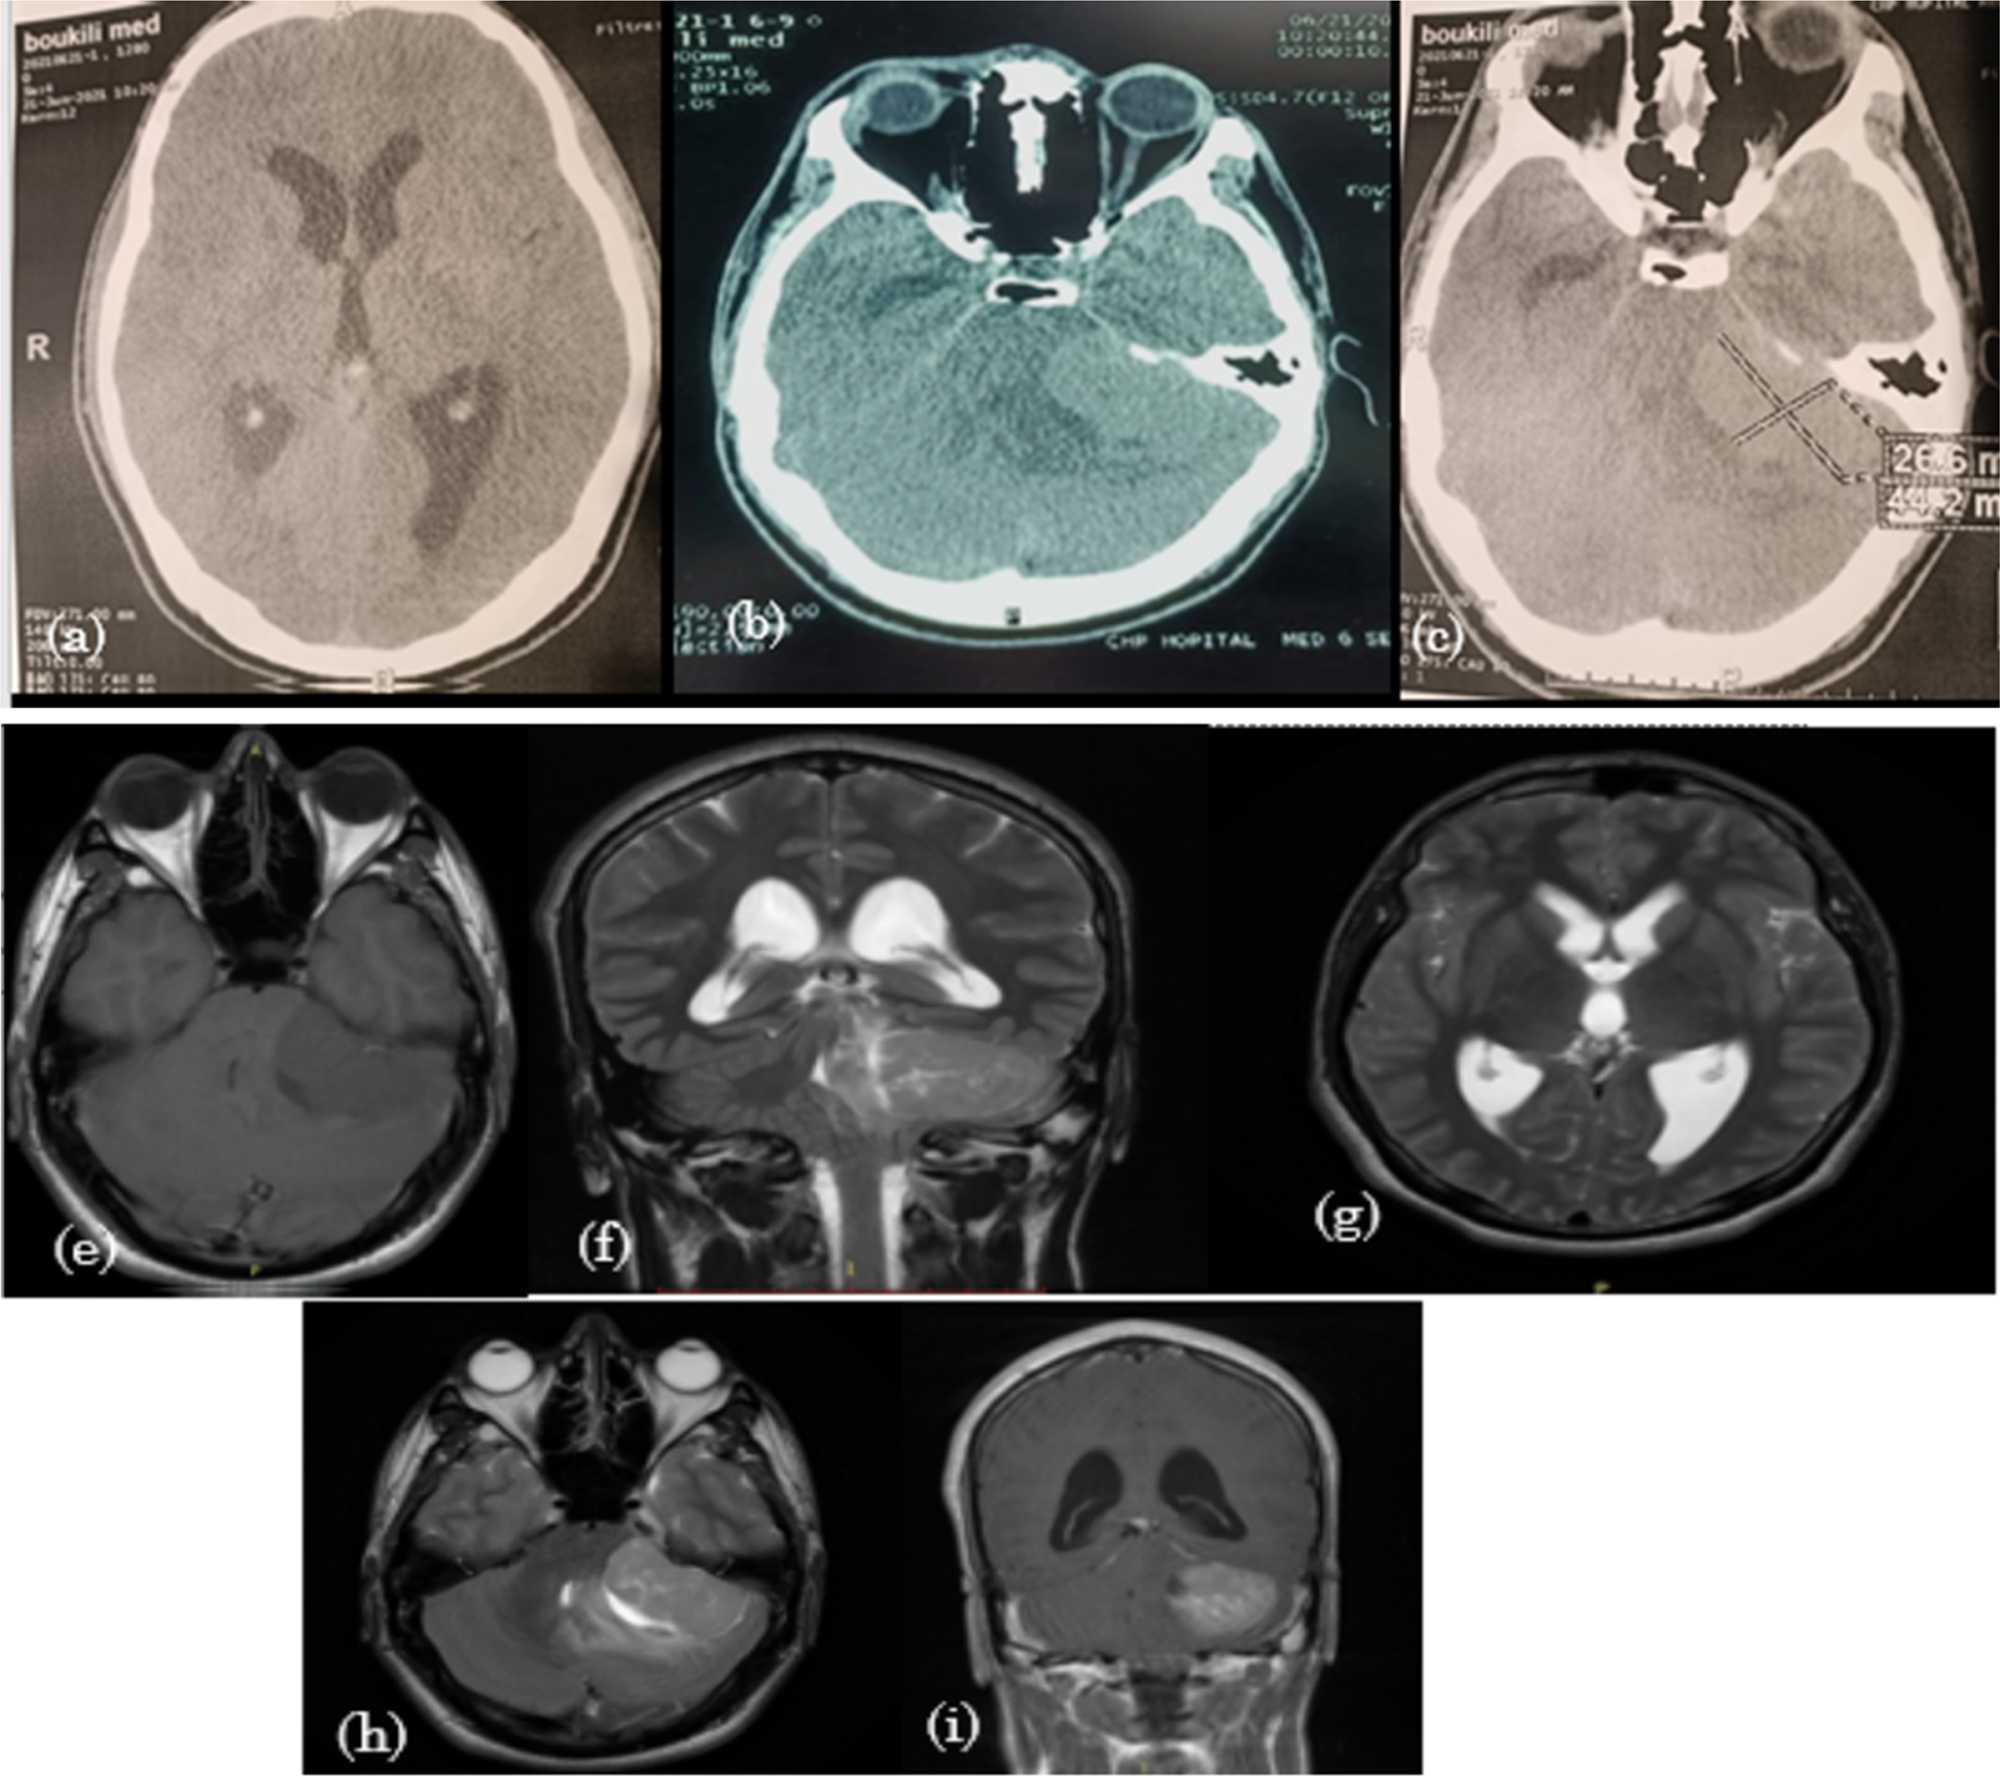

Computed tomography (CT) scan (Figure 1(a)-(c)) and magnetic resonance (MR) imaging of the brain revealed a well-defined extra-axial mass in the left CP angle cistern with a broad dural base causing mass effect on underlying cerebellum and brainstem, with resultant compression and displacement of the fourth ventricle causing upstream obstructive hydrocephalus, there was no metal extension.

Figure 1. Pre-operative brain CT scan (a)-(c) showing an extra-axial mass at the left ponto-cerebellar angle compressing the fourth ventricle and causing tri-ventricular hydrocephalus. Pre-operative brain MRI: (e) Axial T1 showing a hypointense mass and (f) Coronal T2 showing a heterogeneous mass in the left cerebellopontine angle. (g) Axial T2 showing tri-ventricular hydrocephalus. (h) Axial T2 FLAIR showing adjacent cerebellar edema. (i) Coronal T1 after contrast injection showing moderate heterogeneous enhancement and a large tentorial attachment.